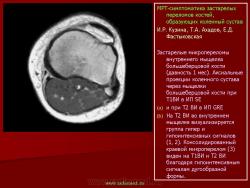

Магнитнорезонансная томография в диагностике повреждений костей голеностопного сустава.

Стрессовые переломы возникают при многократном давлении на кость с величиной, не достигающей критического значения, чтобы привести к острому перелому. Патофизиологически они обусловлены быстрой адаптацией мышц к нагрузке и недостаточной адаптацией к стрессу костей.

Семиотика стресс-переломов аналогична скрытым переломам костей голеностопного сустава и стопы. Дополнительно визуализируется периостальная реакция. Однако в отличие от скрытых переломов патологические изменения визуализируются и рентгенологически.